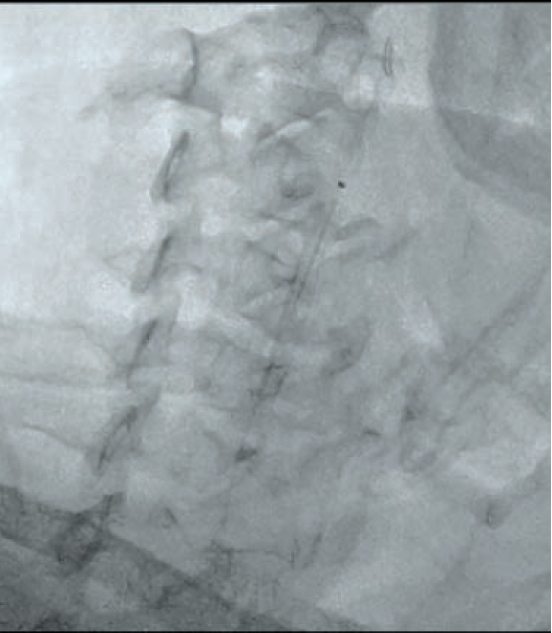

Following aseptic measures and under local anesthesia, a 7 French (Fr) right femoral access was obtained using a routine-length sheath. An .035-inch J-tip guide wire was then parked at the right common carotid artery (RCCA) using a 5 Fr Judkins right catheter, exchanged by a 7 Fr multipurpose guide. This was followed by advancement of a FilterWire EZ (Boston Scientific) across the ostial internal carotid artery stenosis, and deployed in the distal part of the extracranial ICA (Figure 2). After deployment of the FilterWire EZ, a direct stenting strategy was adopted to minimize thromboembolization. A 6 mm x 40 mm self-expanding stent was deployed at the RICA ostium (Figure 3). To our surprise, the view after stent placement showed zero flow into the distal RICA. (Figure 4) The reason appeared to be choking of the filter due to thromboembolization. The filter appeared to be overwhelmed by the volume of the debris captured. A 6 Fr Export catheter (Medtronic) was employed to suction debris from the distal ICA (Figure 5). We also administered pharmacotherapy using intra-arterial nitrate boluses and a weight-based tirofiban bolus. After these measures, there was fair flow into the distal ICA. During the period of no flow, the patient had transient hemispheric ischemic signs and an oropharyngeal airway was required, but his vitals remained stable. These symptoms rapidly resolved after establishment of ICA flow. After establishing blood flow, the proximal half of the stent that remained under-expanded was post dilated using a 4.5 mm noncompliant balloon at 12 atmospheres (Figure 6). Post dilatation, the angiographic view demonstrated good stent expansion and adequate distal flow (Figure 7). The distal protection device was then successfully removed using its retrieval sheath. The final DSA angiogram revealed excellent flow into the distal carotid (Figure 8A) and intracranial vasculature (Figure 8B), confirming no intracranial embolization. The guide was then safely removed over the .035-inch guide wire.